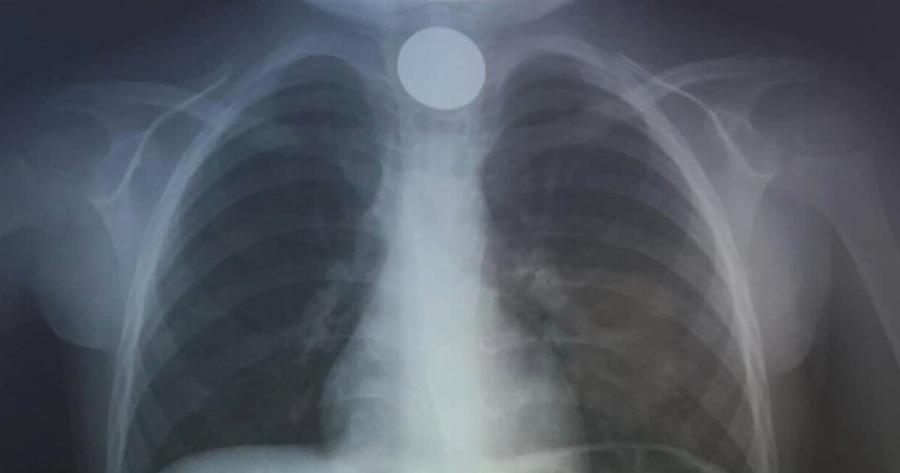

Κατά την άφιξη στο ΠΑΓΝΗ, οι γιατροί προχώρησαν αμέσως σε ακτινογραφία για να εντοπίσουν τη θέση του νομίσματος και στη συνέχεια προχώρησαν στην επείγουσα αφαίρεσή του. Με γρήγορη επέμβαση, οι γιατροί αντιμετώπισαν επιτυχώς την κατάσταση, επιλύοντας γρήγορα το πρόβλημα.